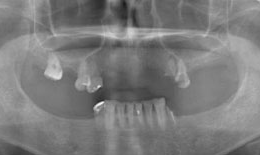

インプラント症例(1)30代 女性

治療前

上顎

保存困難な歯を抜歯後、インプラントを7本埋め込み、セラミックスクラウンを被せた

下顎

保存困難な歯を抜歯後、インプラントを6本埋め込み、セラミックスクラウンを被せた